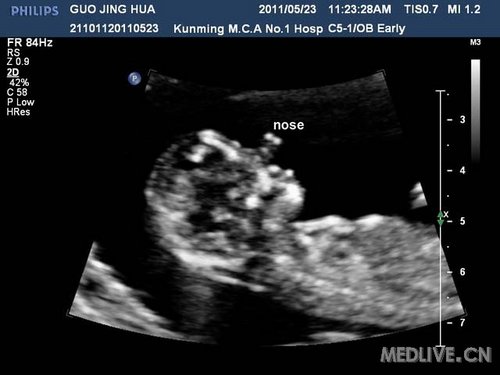

复查时发现:胎儿鼻子位于双眼之间,呈喙鼻状,脑内结构紊乱:正常结构(侧脑室,丘脑)不能很好分辨,不能显示两个侧脑室,两侧丘脑,仅可见一个较大的原始脑室。

诊断为:全前脑,胎儿13-三体可能。建议绒毛活检,孕妇拒绝,要求引产,引产后大体标本与B超相符,取组织做染色体检查,证实胎儿为13-三体。

(2)面部结构严重异常:可出现长鼻畸形或象鼻畸形,单眼眶或眼眶缺失,单眼球,中央唇裂。

(4)眼眶及眼距可正常,扁平鼻。也可合并有严重面部畸形,如猴头畸形,单鼻孔畸形等。